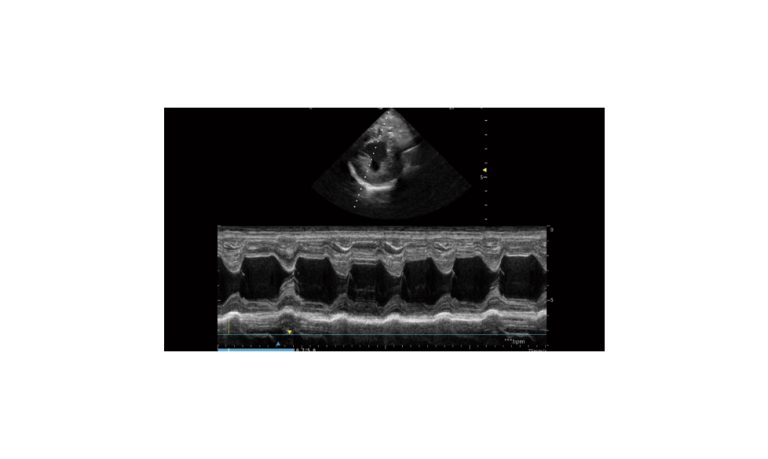

Ultrasound

Wide range of Ultrasound machines that suites a variety of applications from abdominal to rectal scans, we take in consideration how the world is moving towards mobility and mobile applications.

SonoScape Pro Pet E11

Smart Imaging

Introducing the first portable ultrasound with the C-Field+TM platform, redefining diagnostic imaging. Designed for veterinarians, it delivers unmatched clarity, ultra-fast processing, and seamless adaptability for all species. Experience Smart Imaging, Heartfelt Care—anywhere.

Equipped with cutting-edge veterinary software and optimized workflows, it embodies our commitment to Smart Imaging, Heartfelt Care – Wherever Their Journey Leads, with unparalleled performance and adaptability, this innovative system empowers veterinarians to provide exceptional care across all diagnostic applications,

EBIT50/60 VET

All the power you need

The EBit provides all the power you need for today´s challenging clinical environment, yet remain ultra-portable, ultra-affordable. With its cutting-edge imaging technologies, precise and intuitive workflow, ergonomic and eco-friendly design, versatile transducers for all applications from top to toe, we firmly believe the EBit to be the very best portable ultrasound in its class today.

ECO5 VET

Ultra-Portable, Ultra- Affordable, Color doppler

The multi-purpose user presets, comprehensive measurement & report system, built-in EasyView image achieve system, quick image storage / retrieve / transfer, one-button direct print, make the complete workflow better than what you can dream of.